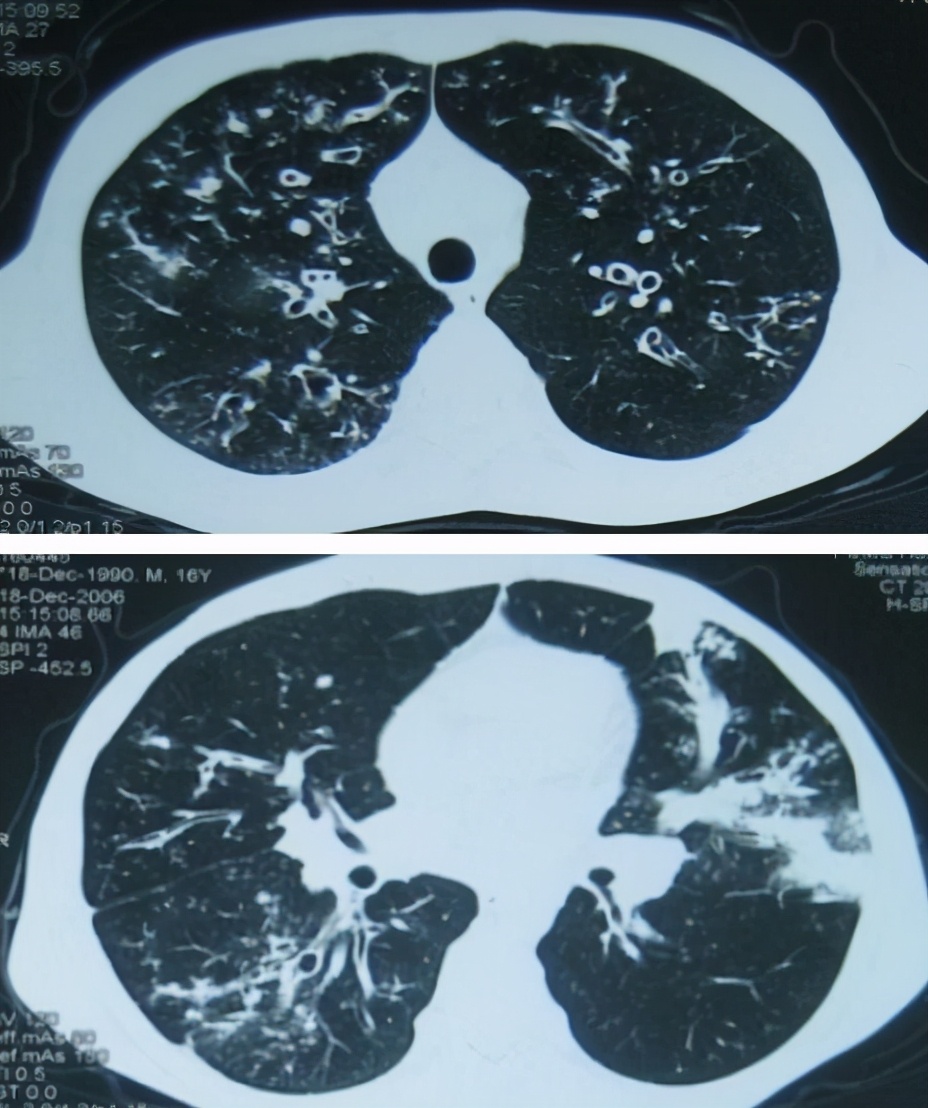

一个16岁的男孩,反复咳嗽、咳痰4年余,加重伴发热3月。胸部CT可见,双肺弥漫性支气管扩张,左肺出现指套征,有片状渗出,经典的支气管扩张的病人。入院后检查发现Serum IgE>5000Ku/L,gm3 (4+),Eos (-)。初步诊断为变态反应性支气管肺曲菌病(ABPA)。

胸部CT